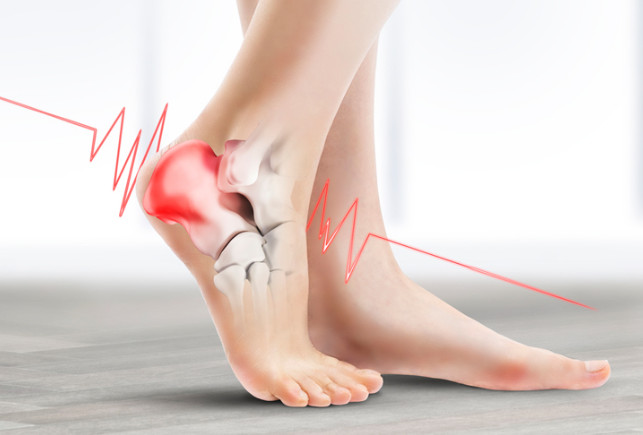

족저 근막염이란?

족저근막염이란 발바닥 뒤꿈치에 염증이 생기면서 나타나는 발바닥 통증을 일컫습니다. 이는 남성보다 여성이 2배 정도 많이 발병된다고 하는데, 그 원인은 과도한 발의 스트레스나 운동으로 인해 발병된다고 합니다. 이 밖에 몸무게의 급격한 증가나 평발도 발병 확률을 높이는 원인이 됩니다.

족저 근막염의 가장 흔한 증상으로는 아침에 통증이 매우 심하다는 점입니다. 그 이유는 밤사이에 족저근막이 수축되었다가 잠에서 깨서 일어나며 지면을 내딛는 순간 스트레칭 되면서 통증이 발생되기 때문입니다. 보통 원인은 종아리의 과단축으로 인하여 발바닥 근막이 당겨지면서 발병하는 경우가 대부분입니다. 때문에 족저 근막염을 예방하려면 평소 종아리와 발바닥을 같이 관리해 주어야 합니다. 만약 족저 근막염에 걸린 경우에는 생활 개선과 함께 필요에 따라 약물이나 의료적 치료가 병행되어야 합니다.